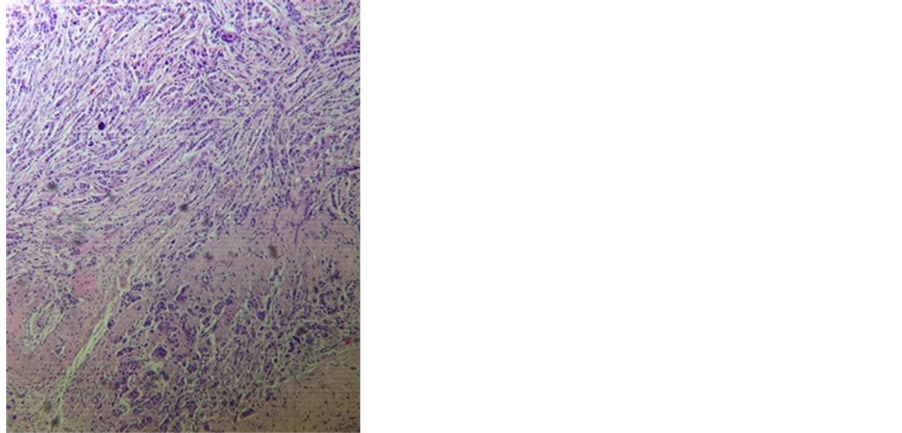

Histological evaluation of the specimen confirmed the diagnosis of invasive ductal carcinoma (Figure 3). However, in addition, granulomas comprising of outer rim of epitheloid cells typical of tuberculosis were seen in a few sections (Figure 4). Histopathological examination of axillary lymphnodes revealed positive evidence of metastasis in the lymph nodes. However there was no evidence of any granuloma. Post-operative recovery

Figure 3. Infiltrating tumor cells (Hematoxylin & Eosin staining, magnification ×10).